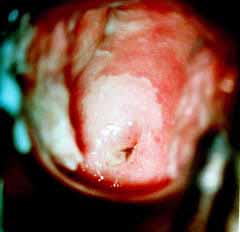

Κολποσκοπικές εικονες για τις αναγκες του forum.